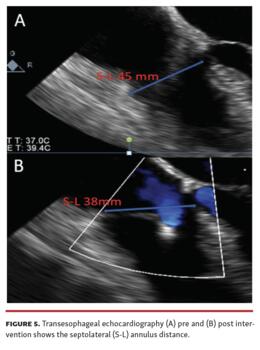

The preprocedural cardiac magnetic resonance (CMR) showed a right ventricular end-diastolic volume index (RVEDi) of 79 mL/m2, right ventricular end-systolic volume index (RVESi) of 27 mL/m2, tricuspid regurgitant volume (TRV) of 56 mL, and tricuspid regurgitant fraction (TRF) of 67% (Figure 3). Due to the patient's history of breast cancer radiotherapy and high surgical risk, the heart team preferred a transcatheter approach as the treatment option. The first TriClip (Abbott Vascular) was successfully implanted in the anteroseptal commissure, determining annulus size reduction and the subsequent necessity of transesophageal echocardiographic projection change to assess the result due to acute reshaping (Figure 4 and Figure 5; Video Series). A second TriClip was implanted in the anteroseptal commissure, highlighting the changes in the valvular plane and cardiac axis (Video Series). Residual TR was trivial (Video Series). The acute remodeling was confirmed at the CMR follow-up (Figure 6), with significant volume and TR reductions (RVEDi, 39 mL/m2; RVESi, 18 mL/m2; TRV, 8 mL; and TRF, 23%).